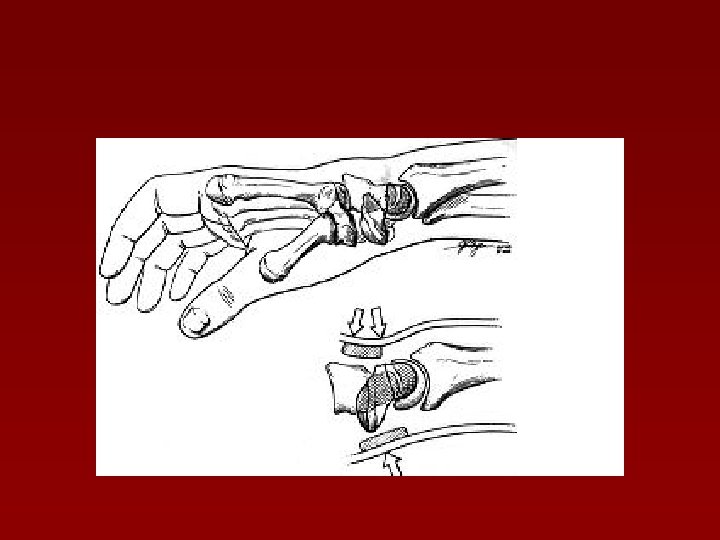

Fracturile osului lunat